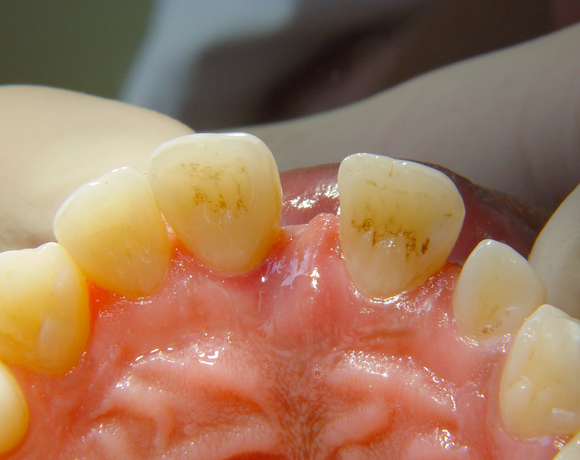

Diese Frontzahnsituation stellte den Behandler vor größere Probleme

Durch Abrasion der Seitenzähne wurden die Frontzähne nach labial verdrängt und lückig. Nach Verlust des Zahnes 41 entstand eine Lücke in der drei Zähne Platz fanden. Auch im Oberkiefer wurden die lateralen Lücken mit Veneers verkleinert.